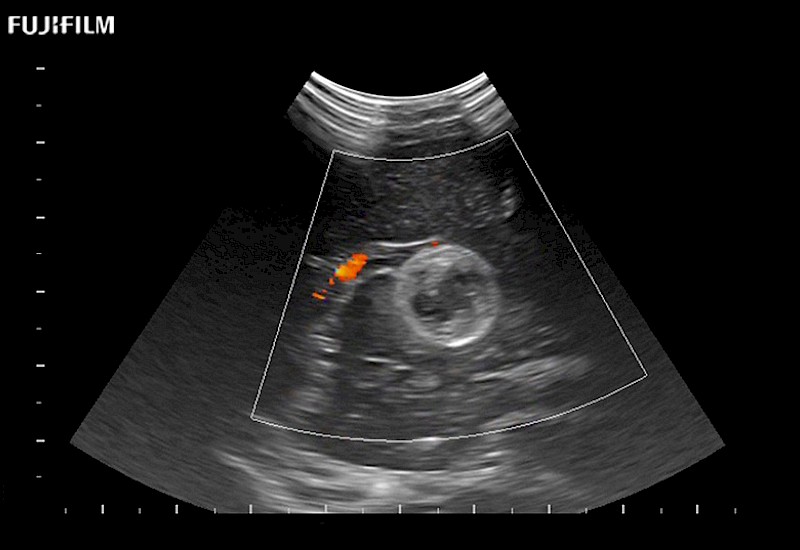

Fujifilm Healthcare understands that neurosurgeons demand excellence in their operating rooms — from their staff and the equipment they depend on. Fujifilm Healthcare's dedication to neurosurgery provides outstanding ultrasound technology, professional support, and the specialized tools necessary to best perform comprehensive real-time ultrasound imaging.

For precise neurosurgery ultrasound imaging, Fujifilm Healthcare offers premium level solutions that include:

Extraordinary high-resolution digital imaging

Exceptional transducers

for use during: Cranial guidance, Burr-Hole guidance, Spinal Cord guidance, Pituitary guidance, Micro-Surgery guidance

Multi-Parametric imaging modalities

Our dedication to neurosurgery allows us to offer superior image quality, outstanding system reliability and intuitive use of cutting edge technology.